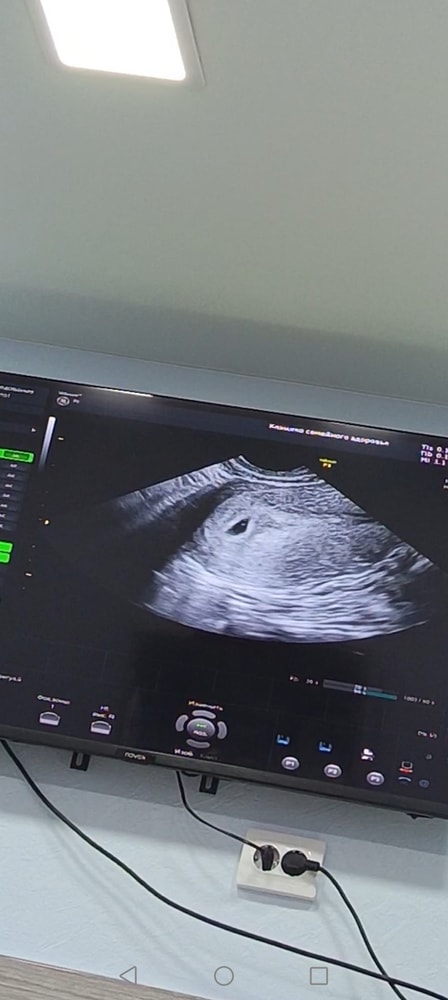

Эмбрион или желточный мешок?

Девочки, снова здравствуйте. Сходила я значит на УЗИ уже платно, прилагаю бумаги.

но вопрос, разве может быть уже и желточный мешок и эмбрион? Или все таки пока просто ЖМ? Но то что кто-то сидит внутри яйца я вижу, самое главное что моя бусинка не пустая)

Ничего себе, такое маленькое плодное яйцо и уже видно эмбриончик в 1 мм. Прям очень хороший аппарат, в следующий раз уже сб послушаете

На втором снимке чётко виден эмбрион с желточным мешком, это уже не просто ЖМ. Сердцебиение должно скоро появиться, если срок подходит. Всё выглядит хорошо.

Ксюша, а сможете объяснить где вы это видите? Я просто поняла черный круг это яйцо, а внутри точка это ЖМ. Исправьте пожалуйста если не так. Срок по узи 5.2, по М-5,5